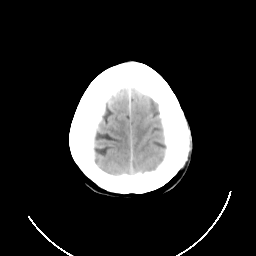

CT Study #3 -- Slice #25

[Home][Help][Clinical][Tour 1] Slice 25